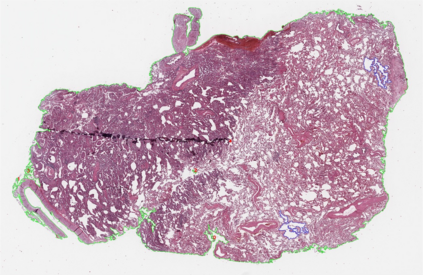

Multiple instance learning (MIL) is a powerful approach to classify whole slide images (WSIs) for diagnostic pathology. A fundamental challenge of MIL on WSI classification is to discover the \textit{critical instances} that trigger the bag label. However, previous methods are primarily designed under the independent and identical distribution hypothesis (\textit{i.i.d}), ignoring either the correlations between instances or heterogeneity of tumours. In this paper, we propose a novel multiplex-detection-based multiple instance learning (MDMIL) to tackle the issues above. Specifically, MDMIL is constructed by the internal query generation module (IQGM) and the multiplex detection module (MDM) and assisted by the memory-based contrastive loss during training. Firstly, IQGM gives the probability of instances and generates the internal query (IQ) for the subsequent MDM by aggregating highly reliable features after the distribution analysis. Secondly, the multiplex-detection cross-attention (MDCA) and multi-head self-attention (MHSA) in MDM cooperate to generate the final representations for the WSI. In this process, the IQ and trainable variational query (VQ) successfully build up the connections between instances and significantly improve the model's robustness toward heterogeneous tumours. At last, to further enforce constraints in the feature space and stabilize the training process, we adopt a memory-based contrastive loss, which is practicable for WSI classification even with a single sample as input in each iteration. We conduct experiments on three computational pathology datasets, e.g., CAMELYON16, TCGA-NSCLC, and TCGA-RCC datasets. The superior accuracy and AUC demonstrate the superiority of our proposed MDMIL over other state-of-the-art methods.